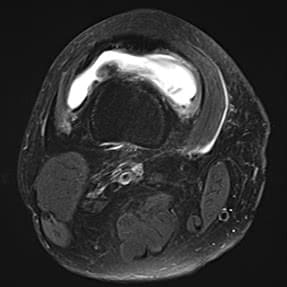

- MRI画像より、変形性ひざ関節症グレード4(末期)と診断。

大腿骨内側に突発性骨壊死があり、半月板も外周へ逸脱

膝蓋大腿関節に水がたまっているのが白く確認できる